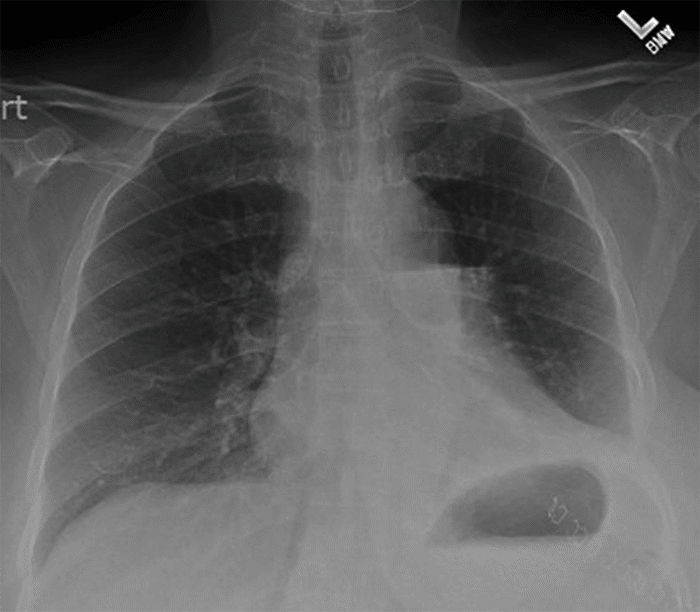

The patient’s postoperative course was uncomplicated, and she was discharged on postoperative day seven. A postoperative chest radiograph, obtained two weeks after surgery, demonstrated good expansion of the upper lobe with a small residual effusion (Figure 4).

Figure 4. Postoperative Chest Radiograph. Published with Permission